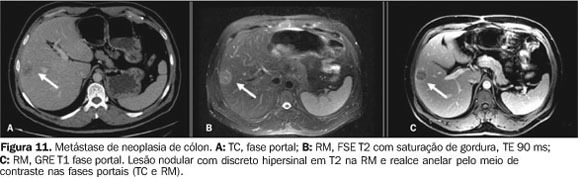

metástase hepatica na RNM

metástases hepáticas mostra diminuição do sinal em comparação com o parênquima hepático normal em imagens ponderadas por T1 e aumento do sinal em imagens ponderadas por T2.

PARECE QUE TEM MASSA DENTRO, NAO É TAO LIQUIDO